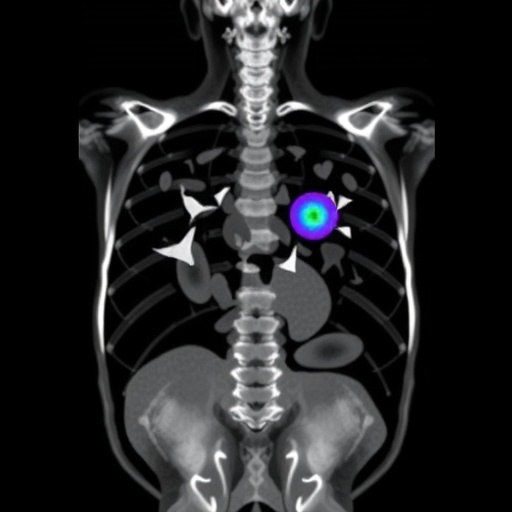

While the technical achievements are impressive, the researchers acknowledge that continued efforts are needed to refine the model’s performance further, especially in segmenting complex or rare anatomical variants. Future research directions point toward incorporating multi-modal imaging data, such as positron emission tomography (PET) fusion, and developing uncertainty quantification methods to highlight cases requiring expert review.